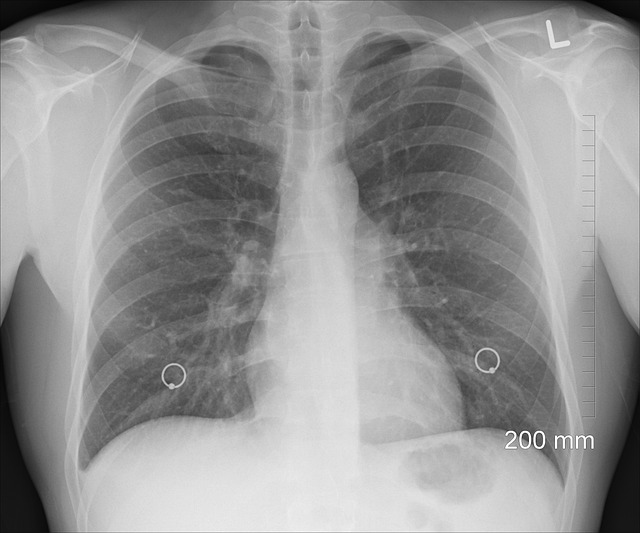

만성 폐쇄성 폐쇄증(COPD)은 주로 유해 물질을 장기간 흡입하여 발생하며, 담배 연기가 주요 원인입니다. 다른 위험 요소로는 직업성 먼지 및 화학 물질 노출, 대기 오염, 유전적 성향 등이 있습니다. 이러한 요인을 이해하는 것은 효과적인 예방 전략을 수립하고 조기에 개입하는 데 매우 중요합니다. COPD의 증상을 인지하는 것은 조기 진단과 개입에 필수적입니다. 지속적인 기침, 천명, 가슴 답답함, 호흡 곤란은 흔한 지표입니다. 진단에는 병력, 신체검사, 폐 기능 검사, 영상 연구가 복합적으로 포함됩니다. 조기 발견은 더 나은 관리와 개선된 예후를 가능하게 합니다.